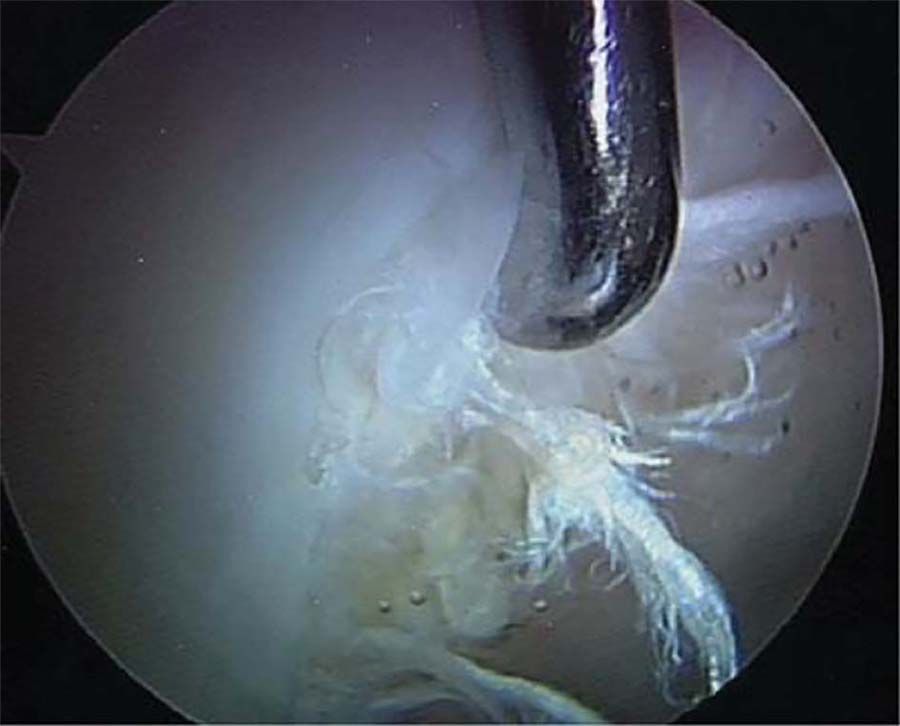

Technique Reconstruction arthroscopique du ligament croisé antérieur par tendon quadricipital autologue , Victoria B. Duthon Centre de Médecine du Sport et de l’Exercice - Hirslanden Clinique de la Colline 76b avenue de la Roseraie - 1205 Genève - tel : +41 22 702 25 41 ema , Jacques Menetrey Centre de Médecine du Sport et de l’Exercice - Hirslanden Clinique de la Colline, 76b avenue de la Roseraie, Genève, Suisse N°268 - Novembre 2017 - Cahier 2 ● 8 min de lecture